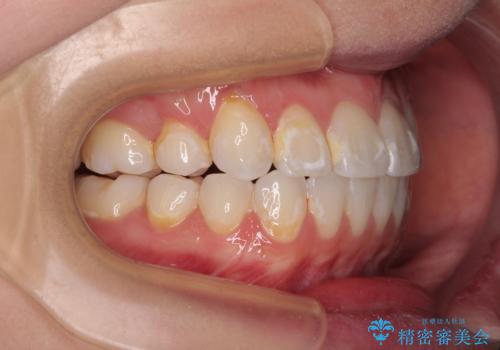

- 八重歯と、それによる正中のズレを気にして来院された患者様です。

口元の突出感は気にしていなかったため、上顎の左右第一小臼歯を抜歯することで、八重歯の解消と上顎の正中を改善していくこととしました。

奥歯の咬み合わせを維持しながら正中位置を改善するために、補助装置を使用しました。

予定より期間がかかりましたが、上下の正中位置を綺麗に一致させることができました。